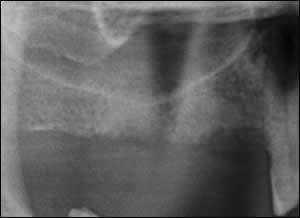

Fig 1: Pre-operative radiograph reveals a low maxillary sinus.